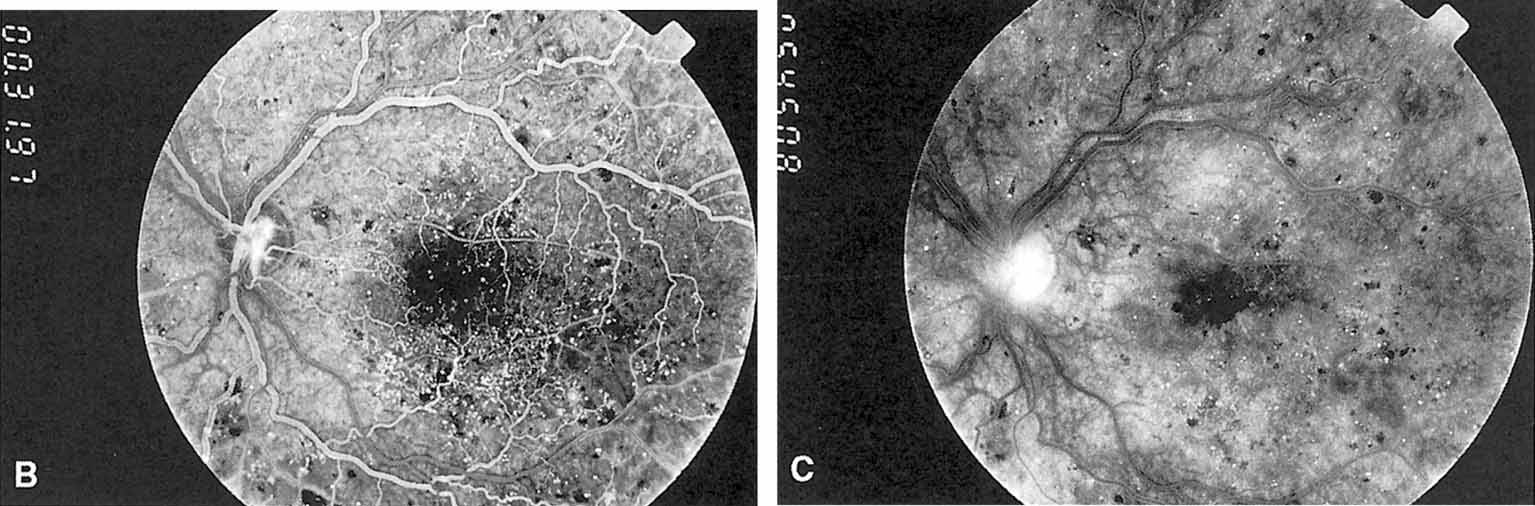

Fig. 3 A. Diabetic retinopathy with multiple microaneurysms, dot hemorrhages, and early neovascularization of the optic disc (NVD). A small blot hemorrhage is seen inferiorly. B. Continued. Midphase of the fluorescein angiogram. Patent microaneurysms are seen as hyperfluorescent dots. Note that most microaneurysms cannot be seen ophthalmoscopically. There is some enlargement of the foveal avascular zone because of some occluded capillaries. Temporally there is a larger zone of capillary nonperfusion. The NVD is beginning to leak. C. Late phase of the fluorescein angiogram showing diffuse leakage of fluorescein into the macula.

It is often difficult to distinguish a small dot hemorrhage from a microaneurysm by ophthalmoscopy alone. On fluorescein angiography patent microaneurysms will fill with dye quickly and then leak,5 unlike a small dot hemorrhage that will block fluorescence (see Fig. 3). However, angiography cannot distinguish a hemorrhage from a microaneurysm filled with clotted blood. Because fluorescein passes easily though them, we usually see many more microaneurysms on fluorescein angiography than are apparent on examination.6

Macular edema (retinal thickening) is an important manifestation of NPDR because it is the leading cause of legal blindness in patients with diabetes. The intercellular fluid comes from both leaking microaneurysms and diffuse capillary leakage. It separates retinal cells, causing multiple intraretinal interfaces which scatter light, decreasing the retina's normal translucency and blurring the normal retinal pigment epithelial and choroidal background pattern (Figs. 3, 4, and 5). Clinically, macular edema is detected by biomicroscopy with a contact lens or by a 60- or 80-diopter hand-held lens. Optical coherence tomography (OCT) is a new diagnostic tool that accurately defines retinal thickness and cross-sectional anatomy (see Fig. 5). In severe cases of edema, the pockets of fluid in the outer plexiform layer are large enough to be seen. This is called cystoid macular edema (CME) (Fig. 6). Usually CME is seen in eyes with other signs of severe NPDR such as numerous hemorrhages or hard exudates, but in rare cases, generalized diffuse leakage from the entire capillary network can result in CME with few other signs of diabetic retinopathy.7

Fig. 4 A Exudates surround an area of hypoperfused retina. Note soft exudate superiorly. The macular edema thickens the retina and obscures the normal choroidal appearance. B. In the center of the hard exudates the fluorescein angiogram shows capillary non perfusion surrounded by microaneurysms. C. The late phase of the angiogram shows leakage into the retina.

In advanced NPDR, signs of increasing retinal hypoxia appear, including multiple retinal hemorrhages, cotton-wool spots (Fig. 7), venous beading and loops (Figs. 7 and 8), intraretinal microvascular abnormalities (IRMA) (see Figs. 7 and 8), and large areas of capillary nonperfusion.

Fig. 7 A. Severe nonproliferative retinopathy with venous dilatation and beading, soft exudates, and intraretinal microvascular abnormalities B. The midphase of the angiogram shows the intraretinal microvascular abnormalities (IRMA) and severe capillary nonperfusion.

Venous beading (see Fig. 7) and venous loops (see Fig. 8) indicates sluggish retinal circulation and are nearly always adjacent to extensive areas of capillary nonperfusion. Focal vitreous traction is thought to contribute to their formation.9 Capillaries next to areas of nonperfusion that dilate and function as collaterals are referred to as IRMA. They are frequently difficult to differentiate from surface retinal neovascularization. Fluorescein, however, does not leak from IRMA but leaks profusely from neovascularization (see Fig. 7).